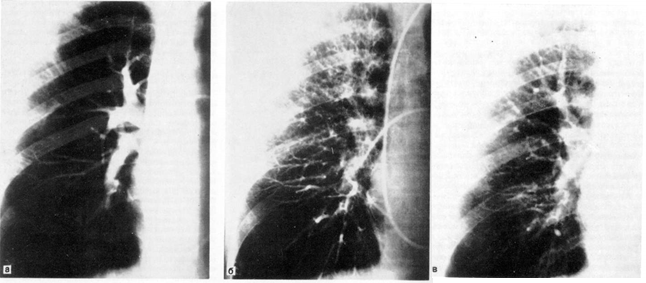

Бронхография легких может быть выполнена под наркозом. Особенность ее проведения заключается в том, что больной лежит на спине, осуществляется искусственная вентиляция легких в условиях миорелаксации. Контрастное вещество вводят через интубационную трубку и в период кратковременного апноэ выполняют рентгенограммы обоих легких в прямой и косых проекциях (рис. 5).

Рис. 5. Поднаркозная бронхография у ребенка. Косая проекция. Норма.